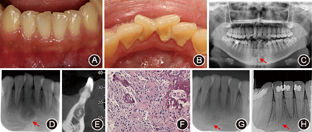

患者女性,16岁,于正畸科拍摄曲面体层X线片时意外发现右下中切牙根尖区呈现低密度透射影像,无自觉症状。

一般检查

未见明显牙体病损,叩痛(-),扪痛(-),无松动,下前牙舌侧可见软垢,舌侧龈缘略红肿,未探及牙周袋(图2A、图2B)。牙髓活力电测试:

(17)。曲面体层及根尖X线片显示:

未见牙体病损,根尖下方可见圆形低密度透射区(1 cm×1 cm),边界清晰,中央可见斑块状高密度影像(图2C、图2D)。锥形束CT示

根尖位于病灶边缘,病灶累及松质骨及唇侧骨壁,唇侧骨壁轻微膨隆,病灶中央有斑块状高密度影像(图2E)。

根尖低密度透射影(箭头);D:术前X线片显示

根尖透射区中心有高密度阻射影像(箭头);E:锥形束CT示

根尖位于病灶边缘,唇侧骨壁膨隆,中心有斑块状高密度影像;F:术中病理切片示富于细胞的纤维结构组织,其中包括层板骨和牙骨质样物质(HE染色 低倍放大);G:术后3个月根尖X线片示

根尖区骨密度升高(箭头);H:术后6个月根尖X线片示

根尖区骨质恢复正常(箭头)

经口腔颌面外科会诊,初步诊断为骨结构不良,建议暂不治疗,定期复查。因患者家属强烈要求明确诊断,遂行手术,术中病理结果为牙骨质-骨结构不良(图2F)。